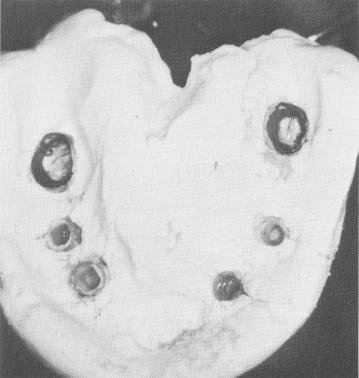

Fig. 11-130. The plaster index with the copings included.